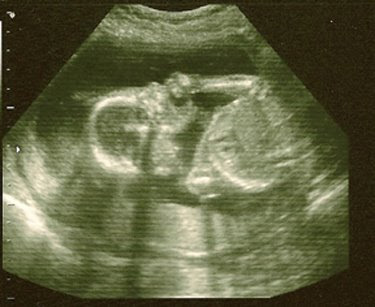

I thought I’d take a break this week from the external belly shots (which were frankly getting a bit dull) and share some internal ones. Here’s the little boxer in one of the few shots where he/she wasn’t flailing its arms around trying to find its own mouth. Once the vital measurements were all taken and the organs accounted for, the three of us got to watch the show. Baby M’s arms would move around, wave to the camera, and then open its mouth and try to put its thumb (or in one case, its whole fist) into its mouth. Then there was a bit of peek-a-boo going on, which reminded us of watching E during one of her ultrasounds. She was a coy thing, always trying to hide behind her hands. This little one wasn’t really shy, just hungry for some fingers. The baby was declared the cutest baby ever on the way home by E and her dad, and when I stare at the photos on my desk all day long, I’d have to say that I agree.

Profile Shot

Snacking on the hand

Little cutie – 12 ounces and 6″ from head to bum – quite a bit of growth since the avocado!